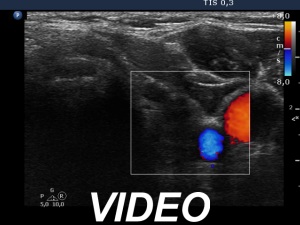

It is worth noting that the FNA of a nodule which is covered with relatively deep ventral non-nodular tissue, necessarily has limitations. Since the success of the non-aspiration sampling technique, we know that the needle collects material from the tissue it passes through without aspiration. Of course, we try to get a sample from the lesion itself by making aspiration only when the needle reached the nodule, but if the needle is blocked during its route to the nodule, this is not always successful. In this patient we made 5 aspirations on 2 occasions. All of the smears showed only Hashimoto's thyroiditis.

The discrete lesion showed see features on which a different pathology could be suspected: in contrast with other hypoechoic smaller areas, the larger lesion was more hypoechoic, had a more regular shape and had microcalcification.

Considering above described circumstances and the significant increase in size, it seemed to be rational to suggest surgery.